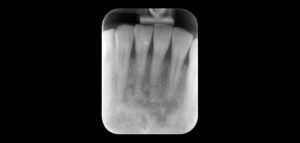

La reabsorción radicular interna (RRI) es una afección inflamatoria que resulta en la destrucción progresiva de la dentina intra-radicular a lo largo de los tercios